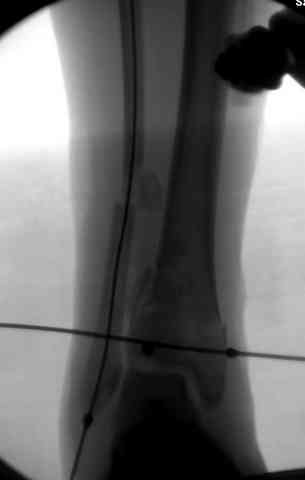

Яков изложил все необходимые аспекты лечения переломов пилона, и, не желая менять тему, решил выставить нашу точку зрения в двух клинических примерах.

При лечении внутрисуставных переломов типа "Pilon"

или "Tibial Plateau" на голени, применение простых

наружных фиксаторов типа "Spanning ExFix" или "Travelling ExFix" стал одним из стандартом этапного лечения.

В первые часы после поступления больным экстренно накладывается простой фиксатор из двух поперечно проведенных стержней или сооружается "Delta

Frame" в зависимости от места локализации, и проводится дистракция.

Здесь выставлена пара случаев перелома пилона, оба

случая леченные этапным наружным фиксатором.

Второй случай фиксирован аппаратом Илизарова.